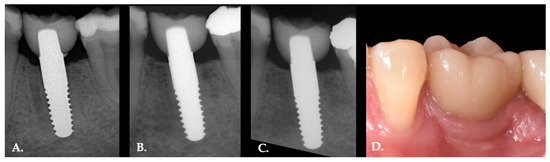

2.2. Clinical Procedures

2.3. Clinical Evaluation

2.4. Radiographic Evaluation

3.3. Radiographic Assessments

4. Discussion